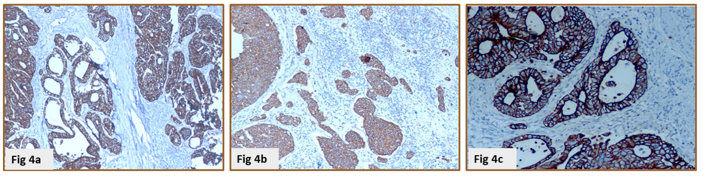

IHC was done on 17 cases in each group (17x3=51 specimens) using two antibodies. The comparison of IHC staining of CTP and LMP methods, LMP and DMP methods (Table 5) in terms of four different parameters in IHC-stained slides was done (Figure 4). A detailed comparison of DMP and LMP with existing literature is provided in Table 6 and 7.

Figure 4. Comparison of IHC of a slide of adenocarcinoma with Pancytokeratin - Conventional tissue processing (a), laboratory microwave processing (b), and Domestic microwave processing (c) shows equally good intensity and localization of antigen (DAB 100x)